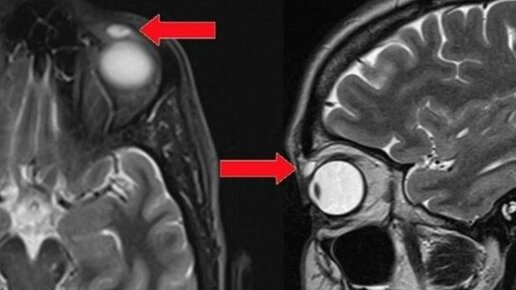

Врачи во время простой операции достали у пациентки из глаза деформированную линзу. Оказалось, посторонний предмет находился в органе зрения женщины с раннего детства. В Шотландии 42-летняя женщина обратилась к врачам небольшой деформации глаза. Специалисты решили, что у пациентки киста: визуально место повреждения выглядело как самое обычное вздутие. Но на операции врачи обнаружили в глазу женщины полупрозрачное тело, внешне напоминающее скорлупу. Оказалось, это была контактная линза. Только вот пациентка не пользовалась этим способом коррекции зрения уже больше 20 лет...